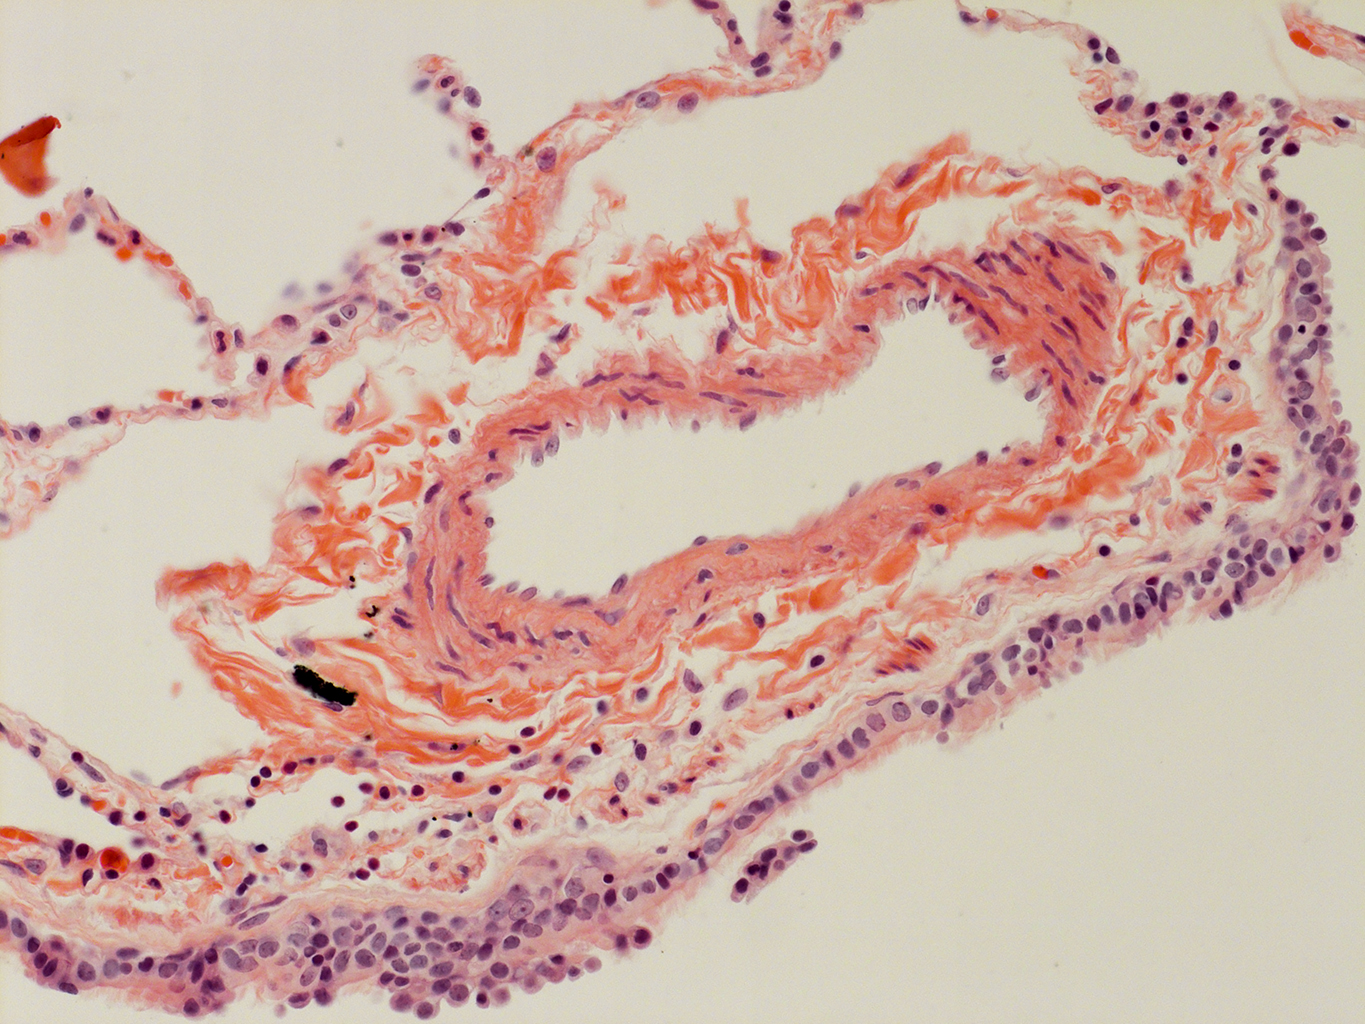

Donor tissue kindly provided by Dr. Scott Randell, University of North Carolina

Tissue Used:

LMHA-15-UNC-2017-12-19_D0037L.05HP_3_48

Gender: Male

Age:Â 43 Year Old

Race: Hispanic

Non-Smoker